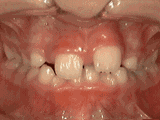

Crowding of the teeth

Patient started treatment at age eleven and wore braces for twenty-six months. He loves his new smile.